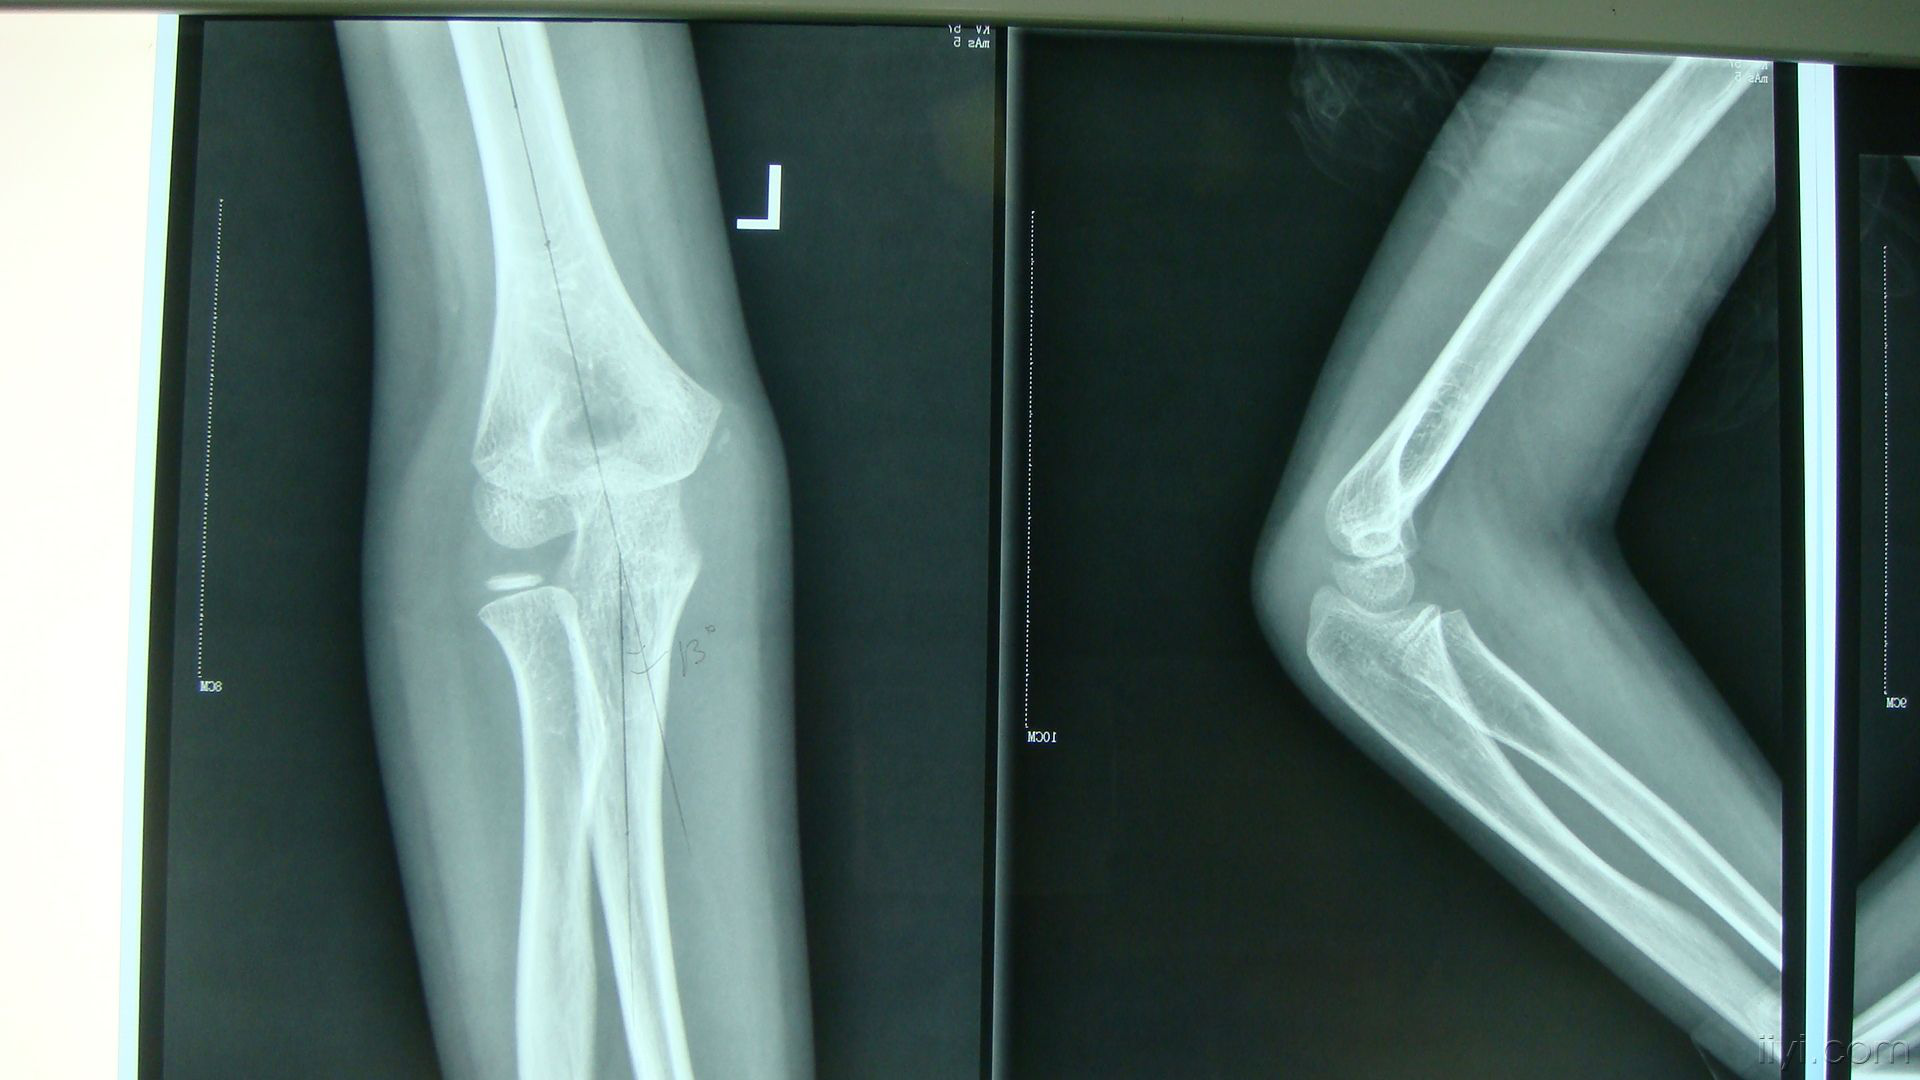

疾患・症状 疲労骨折とは何か?起こる原因と部位、予防法など 疲労骨折という言葉を耳にしたことはありますか? 骨折というと骨がポッキリ折れてしまうことをイメージするかもしれませんが、疲労の積み重ねによって起こる場合もあります。肘部管症候群 テニス肘(上腕骨外側上顆炎) 肘内障 上腕骨顆上骨折 野球肘 変形性肘関節症 前骨間神経麻痺・後骨間神経麻痺 尺骨神経麻痺上腕骨外顆骨折は肘の外側のくるぶしに起こる骨折で、幼少期の骨折の中では上腕骨顆上骨折と同じぐらいの頻度で遭遇する骨折です。 症状 肘の外側のくるぶし(上腕骨外側顆)に圧痛・腫脹・皮下出血が見られ、肘の屈伸や前腕の回旋運動により疼痛

小児上腕骨顆上骨折 一般社団法人 日本骨折治療学会 骨折の解説

こどもの肘骨折 稲毛整形外科

肘関節がらみの骨折